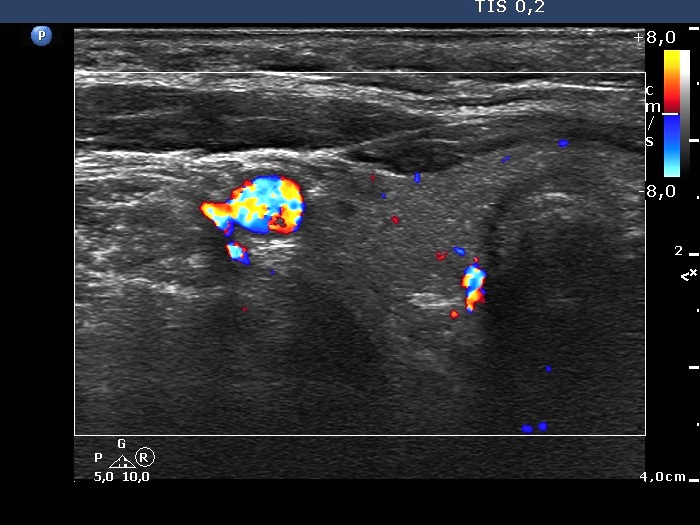

Benign nodular hyperplasia - Case 50. (ultrasonographic picture 3)

Right lobe, horizontal scan, color Doppler mode. The vascularization is average or a bit decreased.